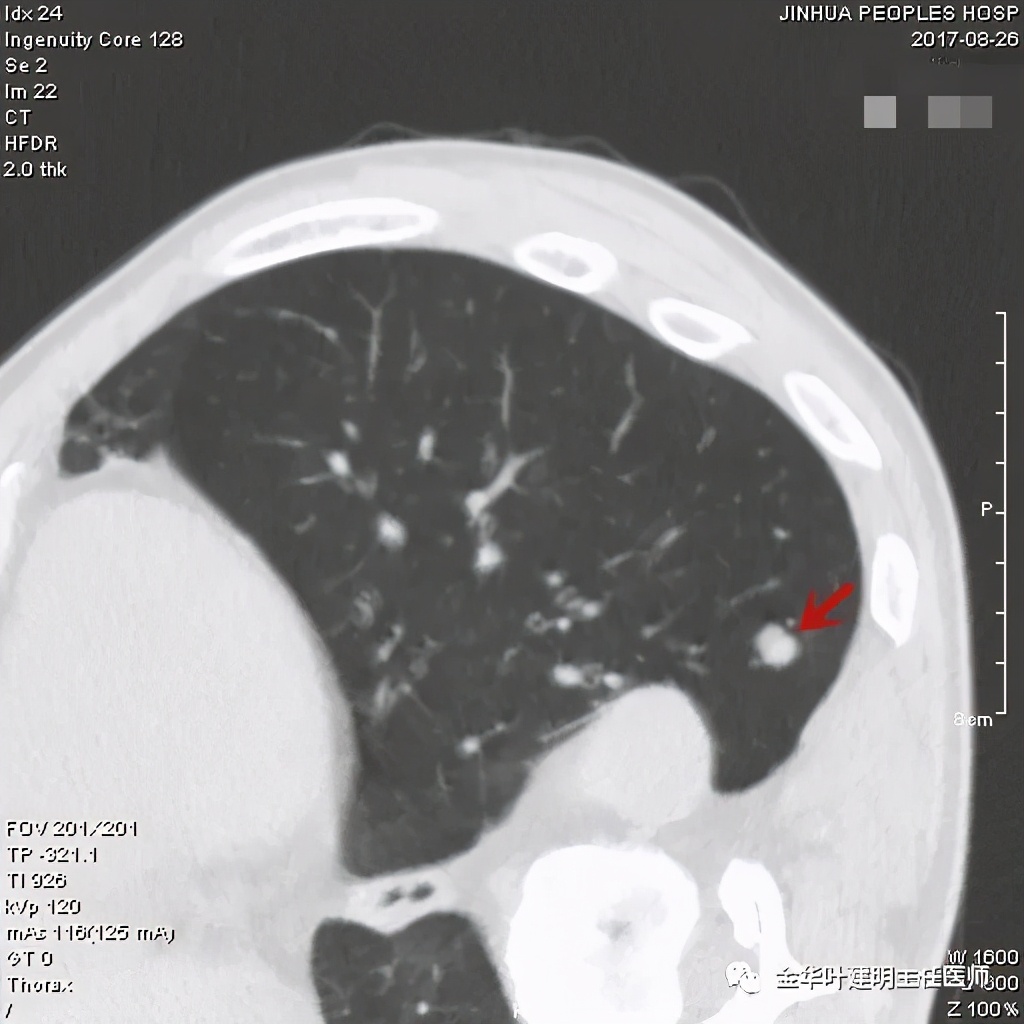

其实今天分享这个病例与我们以往的错构瘤不太一样,以前的影像如下:

密度略不均,但边界甚清,边光峭

周围,边缘非常清,病灶内部有点状高密度,约1厘米许,似有微血管征

密度非常高的结节,边缘非常光滑

周围,边缘非常光滑,缺乏收缩力

高密度,周围,边缘非常光滑,亚厘米

高密度,边缘非常光滑,周围

这个也比较大,但边缘非常光滑,密度相对较为均匀

其实我们发现,包括今天这例,只要是错构瘤,“边缘非常光滑”是每一像都具备的!虽然有的似有支气管截断、有的似有血管征、有的似有分叶,但总的只要是边缘非常光滑的实性占位,就要想到错构瘤的可能,若有点状钙化密度,更是强烈要考虑。错构瘤如何靠近胸膜,其实可以切开一点肺实质,挤一下,肿瘤就会滚出来。